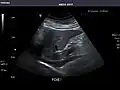

Left kidney -

Kidneys: Right and left kidneys measure 11.5 cm and 12 cm in length respectively. No hydronephrosis. Small left lower pole kidney cyst.